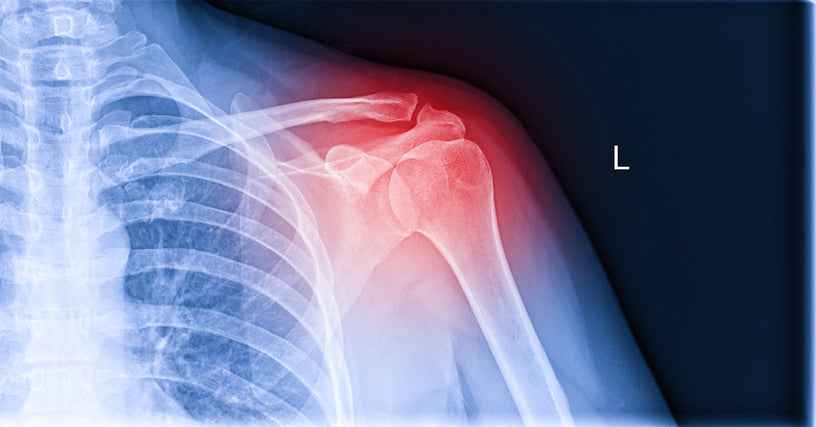

What does a rotator cuff injury look like?

A rotator cuff tear may present as persistent shoulder pain, especially when lifting or rotating the arm. Individuals might experience weakness, a clicking sensation, or difficulty reaching overhead.